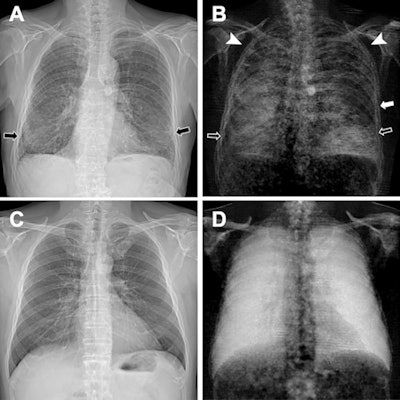

The patient (Fig 2: A, B) demonstrated substantially decreased dark-field signal in the upper lungs (left more than right), where emphysema is most severe, and inhomogeneous but decreased lower lung signal (due to presence of fibrosis) when compared with a healthy subject (Fig 2: C, D). The stronger manifestation of fibrosis in the right lower lobe compared with the left lower lobe, as was seen on CT images, corresponded well to the asymmetric reduction of dark-field signal in the lower fields with a right-sided predominance (Fig 2B), the authors wrote.

"As both fibrosis and emphysema lead to a reduction of dark-field signal -- due to a smaller number of intact alveoli -- the assignment of signal loss to one of the two pathologic conditions is hardly possible from the [dark-field chest x-ray] alone," the researchers wrote.

However, the combination of conventional and dark-field images might allow for the differentiation of emphysema and fibrosis, especially as the images are perfectly coregistered, they suggested.